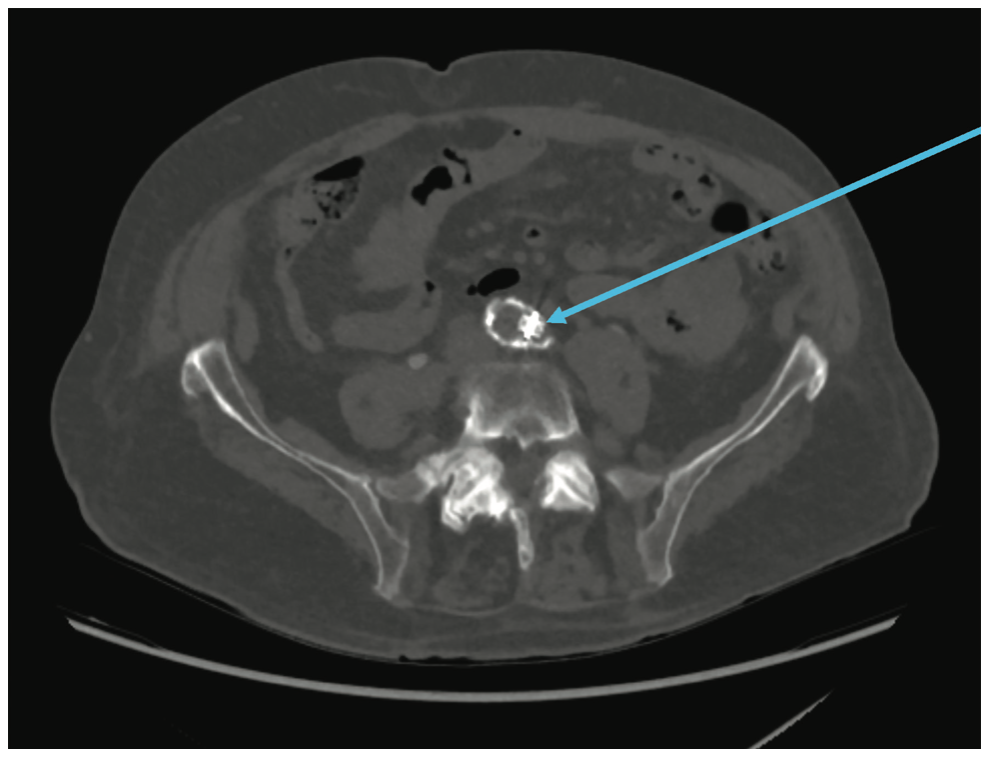

The patient’s speech improved; however, there was concern as to the cause of the diffuse acute stroke. A CTA of the thorax was ordered to evaluate the LAA/Watchman device. A leak was present in the LAA measuring approximately 5.88 mm (Figure 3), similar in size to the leak noted prior to the AVP2 device placement. Subsequent CTs of the lower abdomen, pelvis, and extremities revealed the AVP2 was lodged at the origin of the left common iliac artery (Figure 4). The plug had become dislodged from the LAA and traveled through the aortic arch to the abdominal aorta. Retrieval of the plug was planned for 5/31/22.